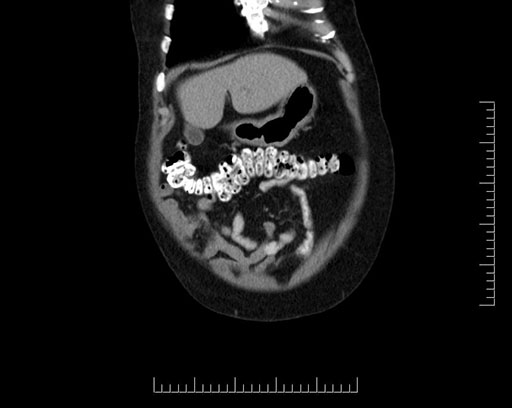

Imaging Analysis

Look through the patient's CT scan to identify any areas of concern for the necessary procedure.

Based on your CT findings, which issue(s) would give reason for "planned slowing down moment(s)" in this case?